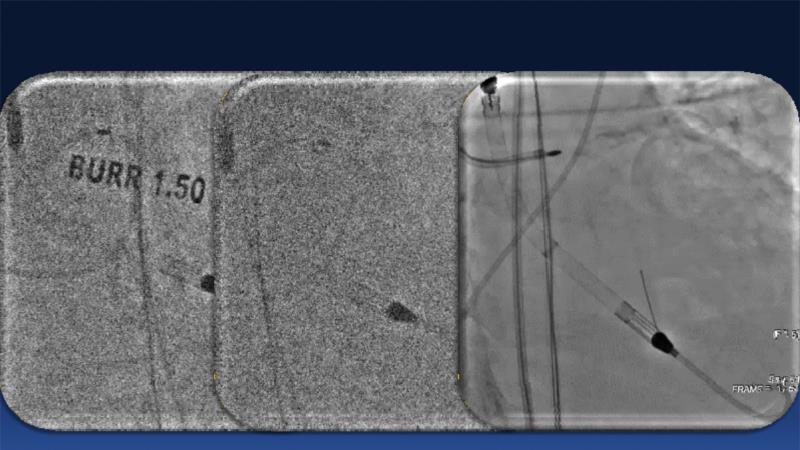

Over the last five years, we have learned that there is a new tool for treating calcium, the greatest enemy of interventional cardiology, which can take various forms: intravascular lithotripsy. In this session, look at how to master this technique in different scenarios, from eccentric calcified lesions to left main bifurcations.

- To understand the mechanism of action of intravascular lithotripsy (IVL) for the treatment of calcified lesions